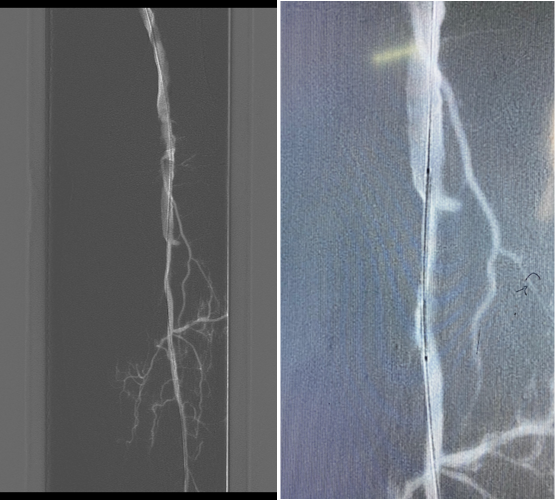

图:术中

图:手术结果